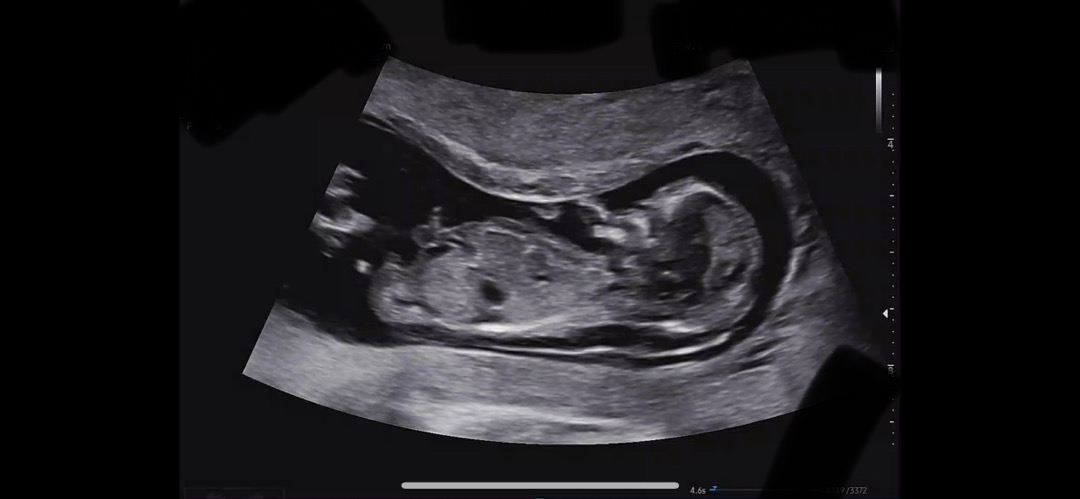

각도법 봐주시면 감사드 드리겠습니다(12주)

남자일것만 같은 느낌적 느낌은 제 기분인거겠죠? 투명대 3.9 나와서 니프티 하고왔는데 기분이 울적하네요 ㅜ괜찮길..